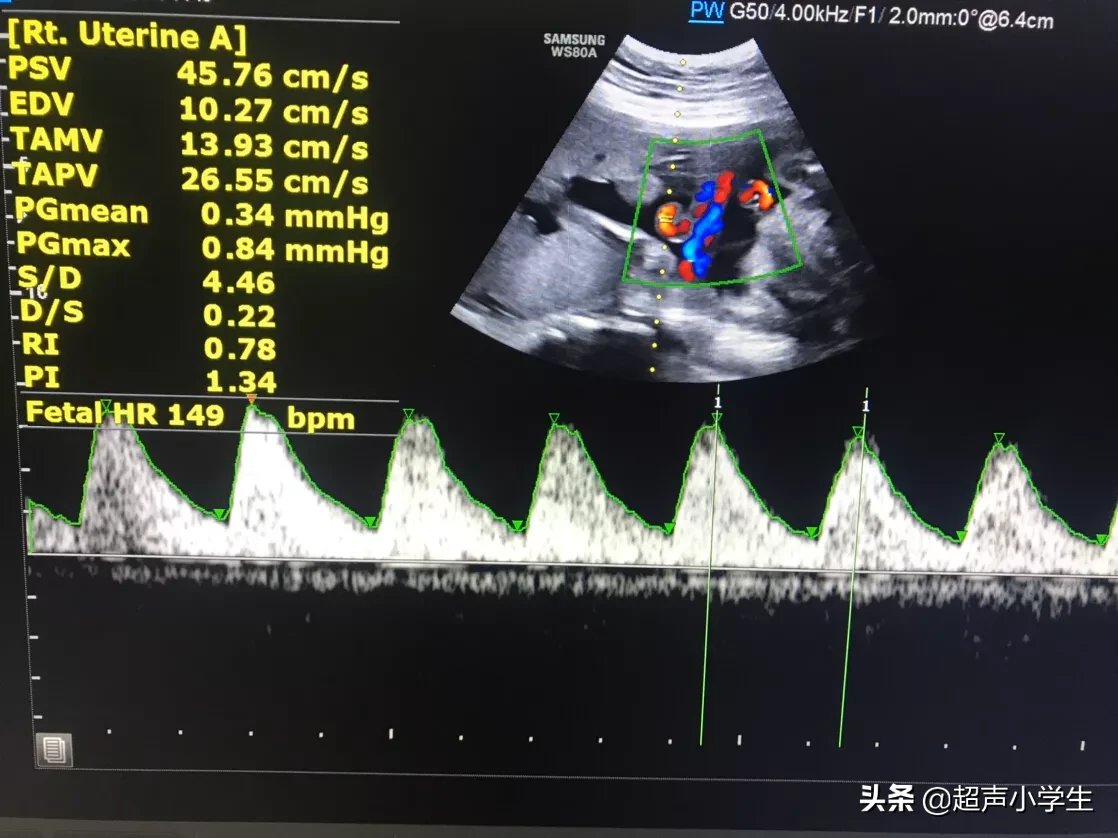

胎心率正常情况该是什么样的?正常情况下胎心率为120~160次/分钟 。所以胎心率不会是一个固定的值 , 而是在一般在安全范围内浮动 。既然不是固定的值 , 就会有高有低 , 我们在检查报告上看到的胎心率的值只是胎儿某一时刻的胎心率值 。

一般来讲宝宝动的时候胎心率高一点 , 宝宝睡着了胎心率低一点 , 胎心率是真的和性别没有关系 。